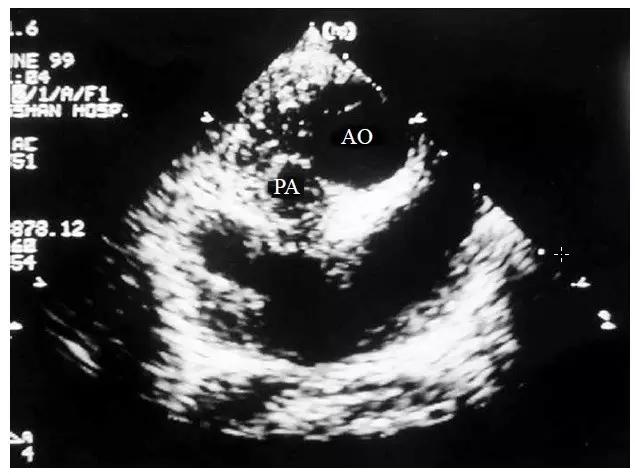

胸骨旁大动脉水平短轴切面能准确反映两根大动脉的空间位置关系,故可作为判断主动脉为左型转位抑或为右型转位的诊断根据。在此切面上,可见两根大动脉的根部同时被横切,呈现一前一后排列的两个圆形大血管横断图像,其外层表现为圆环状,内部为无回声管腔,正常情况时的肺动脉从左侧环绕主动脉半周而向上延续的交叉走行图像消失。若前位的主动脉位于后位的肺动脉的正前方或右前方为右型大动脉转位(图10-4-5);若前位的主动脉位于后位的肺动脉的左前方则为左型大动脉转位(图10-4-6)。

图10-4-6 左型大动脉转位的二维超声心动图表现

胸骨旁大动脉水平短轴切面显示主动脉(AO)位于肺动脉(PA)的左前方